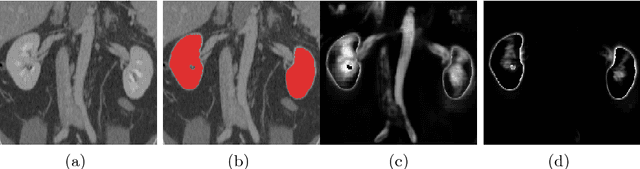

Abstract:Training deep neural networks on large and sparse datasets is still challenging and can require large amounts of computation and memory. In this work, we address the task of performing semantic segmentation on large volumetric data sets, such as CT scans. Our contribution is threefold: 1) We propose a boosted sampling scheme that uses a-posterior error maps, generated throughout training, to focus sampling on difficult regions, resulting in a more informative loss. This results in a significant training speed up and improves learning performance for image segmentation. 2) We propose a novel algorithm for boosting the SGD learning rate schedule by adaptively increasing and lowering the learning rate, avoiding the need for extensive hyperparameter tuning. 3) We show that our method is able to attain new state-of-the-art results on the VISCERAL Anatomy benchmark.

Abstract:Deep convolutional neural networks (CNNs) have shown excellent performance in object recognition tasks and dense classification problems such as semantic segmentation. However, training deep neural networks on large and sparse datasets is still challenging and can require large amounts of computation and memory. In this work, we address the task of performing semantic segmentation on large data sets, such as three-dimensional medical images. We propose an adaptive sampling scheme that uses a-posterior error maps, generated throughout training, to focus sampling on difficult regions, resulting in improved learning. Our contribution is threefold: 1) We give a detailed description of the proposed sampling algorithm to speed up and improve learning performance on large images. We propose a deep dual path CNN that captures information at fine and coarse scales, resulting in a network with a large field of view and high resolution outputs. We show that our method is able to attain new state-of-the-art results on the VISCERAL Anatomy benchmark.